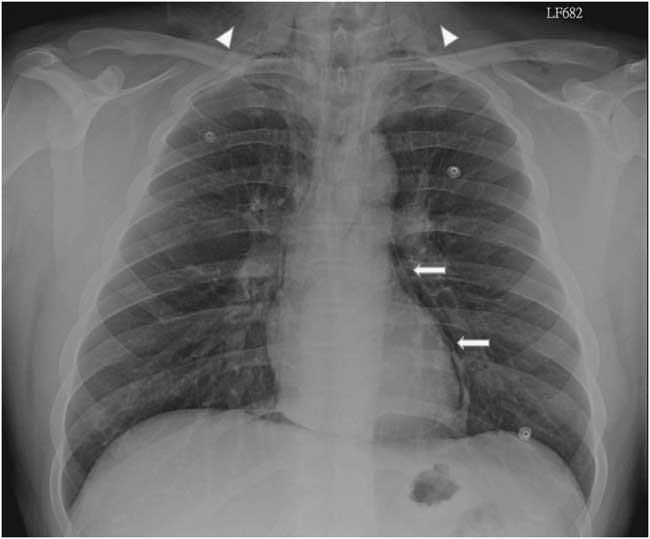

A 22-year-old male presented to the emergency department due to progressive odynophagia and dysphagia. He underwent a left third mandibular molar extraction at the dental clinic a week prior. At the emergency department, vital signs were normal except tachycardia (114/min) and tachypnea (22/min). A physical examination revealed bilateral neck tenderness with crepitus on palpation, no stridor or acute airway compromise signs. Laboratory data showed leukocytosis (white blood cell count, 19000/cumm; segmented, 91%) and elevated C-reactive protein (1.07 mg/dL). Radiographs showed the presence of prevertebral emphysema on the C-spine lateral view (Figure 1) and subcutaneous emphysema with pneumomediastinum on the chest posteroanterior view (Figure 2). A non-contrast computed tomography (CT) scan confirmed the radiographic findings; additionally, there was gas collection over the pericarotid, pericardial (Figure 3) and extradural spaces (Figure 4). Because there was no CT evidence of infectious signs and clinical features were stable, conservative treatment with intravenous amoxicillin/clavulanic acid was given for a week. Clinical symptoms improved, and a follow-up CT showed no residual gas.

Figure 2 Posteroanterior chest radiograph shows subcutaneous emphysema (arrow heads) and pneumomediastinum (arrows).